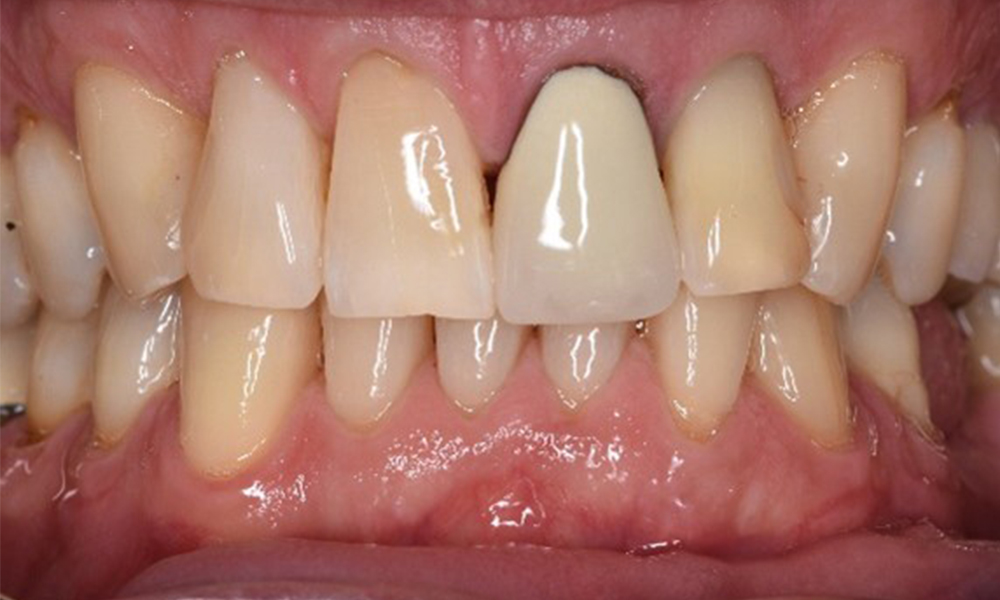

Fallpräsentation: Management komplexer Zahnprothetik

Es ist längst bekannt, dass Mundgesundheit und Allgemeingesundheit in direktem Zusammenhang stehen und einen zum Teil bidirektionalen Einfluss aufeinander haben. Die Berücksichtigung beider Faktoren sind bei der Planung der oralen Prävention und Therapie der Patienten in der Zahnarztpraxis unabdingbar. Dabei ist oberstes Ziel, die Gesundheit und die Lebensqualität der Patienten sowohl aus zahnmedizinischer -und medizinischer Sicht zu erhalten. mehr Infos